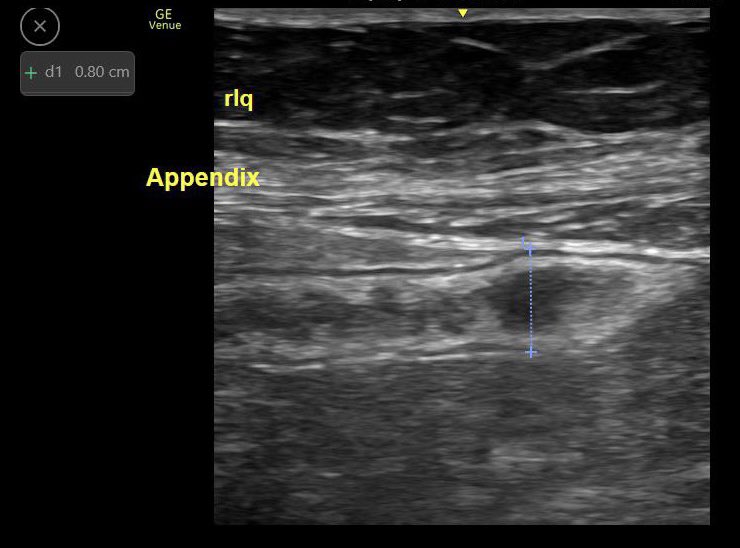

That feeling when you teach residents how to find an appendix on Thursday and they find this on Friday 🤗 #POCUS #fmpocus